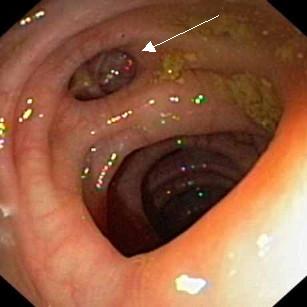

Image macroscopique d' endoscopie de

diverticule du colon est tres particuliairement :

Aspect macroscopique d'une

diverticule seul du colon . En vue si nette . |

Image completement de trois

diverticule tres pres d'une haustral du colon .

Diverticulose colique. |